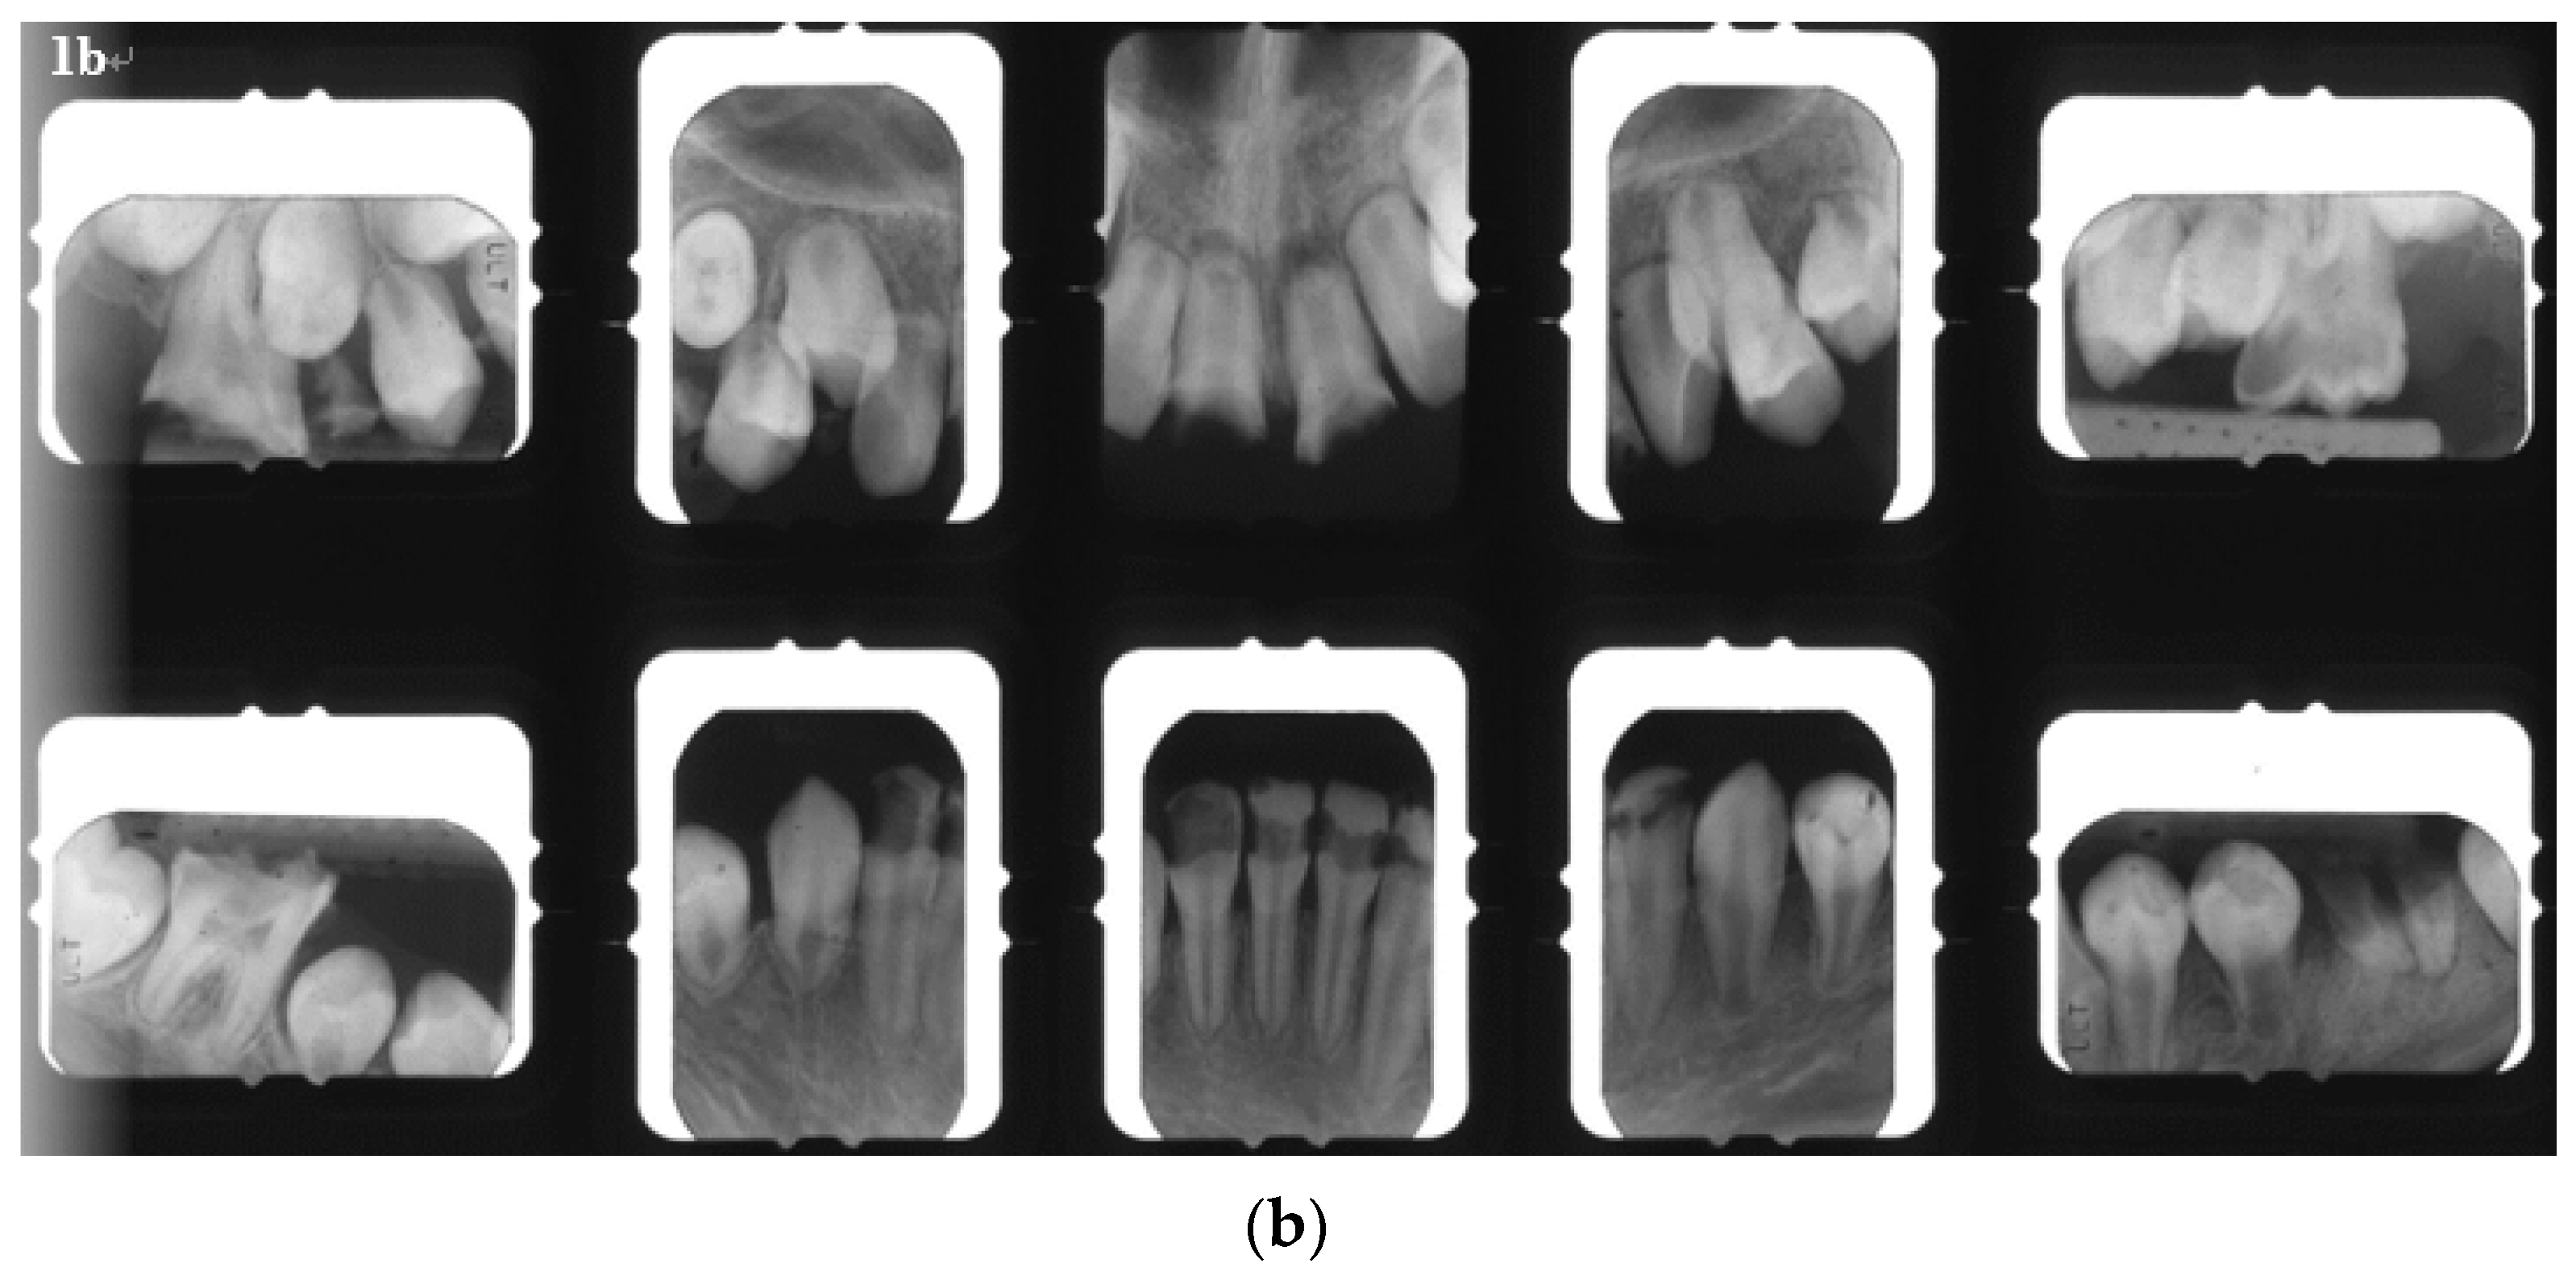

2. Case Report